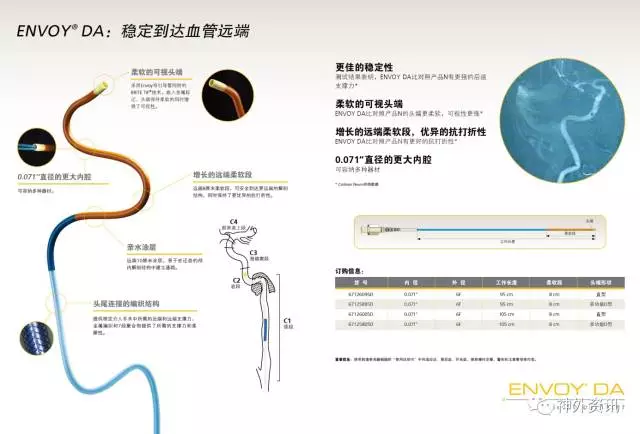

众所周知,传统的Envoy支撑性好,到位较低,满足大部分颅内血管的临床需要,对于血管严重迂曲和复杂动脉瘤的治疗需要导管提供更高的支撑力和更好地顺应性,所以有着更柔软头端,比普通导引导管上的更远的远端通路导引导管更能满足临床需求。

ENVOY® DA 远端通路导引导管在介入手术中可以突破颈内动脉岩谷段到达更远端甚至更下一级血管,在一些复杂颅内动脉瘤、终末支血管供血的AVM以及病变近端通路迂曲的情况下为微导管及支架导管提供了稳定的支撑力,为介入手术的成功提供了保障。

1. Envoy DA远端通路导引导管,是强生公司在Envoy导引导管的基础上研发的产品,在保留Envoy近端支撑力的同时,柔软的8cm柔软段能很好的锚定在迂曲的颅内血管中。对于绝大部分的神经介入复杂治疗不需要使用长鞘,为手术提供了便利。

2. 病变血管迂曲的复杂动脉瘤、终末支血管供血的AVM一直是神经介入手术的治疗难点,远端通路导引导管Envoy DA能够为微导管提供更好的稳定性和支撑力,为这类手术的成功治疗提供了保障。